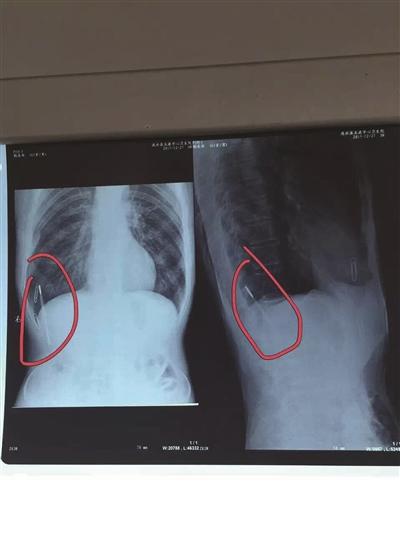

医护人员从嵇老汉体内取出的体温计。贾亮 摄

今年65岁的嵇老汉前不久因一件小事受伤,到淮安市涟水县医院拍片检查时,被告知其体内有异物,这可吓坏了嵇老汉,想起自己内侄在涟水五港卫生院,于是来到该院找内侄帮忙,结果,卫生院的医护人员于17日上午在老汉体内取出一根医用水银体温计。

对嵇老汉检查显示,他的体内有根体温计。

据涟水县五港医院的邵主任和贾医师介绍,嵇老汉体内的体温计存在于体内的腹肌与胸肌之间,十分危险,如果不是这次偶然发现,生活中一旦遇到外力,就很可能戳穿其他内脏,那样生命安全就很成问题,或者体温计破裂也就出事了。不过,对于嵇老汉体内的体温计是什么时候进去的,为什么会进去,嵇老汉自己也说不清,目前仍是个谜。